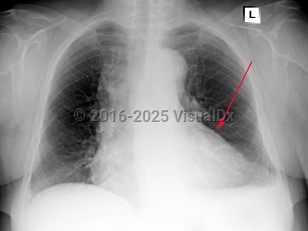

Pericarditis

Symptoms and Signs: Acute pericarditis typically presents with sharp pleuritic chest pain, exacerbated by the supine position and improved with leaning forward. Fever and myalgias may be present but are not required features. On examination, a scratch-like friction rub (pericardial rub) may be heard, although this is present in less than 33% of cases. To make the diagnosis of pericarditis, the patient must have 2 of 4 criteria: pericardial rub, chest pain, ECG changes, and/or presence of a pericardial effusion. Chest pain has the highest incidence and is seen in 85%-90% of cases.

While not usually life-threatening, acute pericarditis can progress to cardiac tamponade or constrictive pericarditis in some complicated cases. Consider constrictive pericarditis in cases of unexplained heart failure. Tricuspid regurgitation is common in these patients and is associated with increased mortality. Other findings in constrictive pericarditis can include Kussmaul sign (a paradoxical increase in jugular venous pressure on inspiration), jugular venous distention, peripheral edema, hepatomegaly, and pericardial knock.